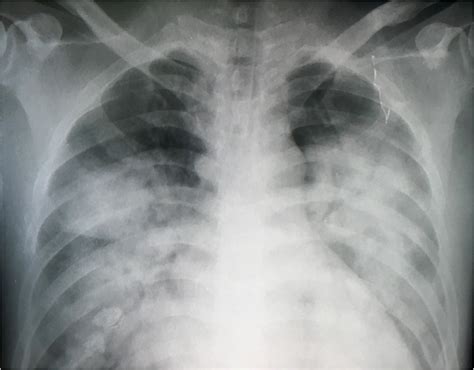

ARDS is a complex syndrome that can be triggered by various factors, including sepsis, pneumonia, trauma, and aspiration. It is marked by the rapid onset of bilateral pulmonary infiltrates, refractory hypoxemia, and decreased lung compliance. The Ards Chest X Ray is instrumental in visualizing these pulmonary infiltrates, which appear as diffuse, bilateral opacities on the radiograph.

The Ards Chest X Ray is often the first imaging modality used to evaluate patients suspected of having ARDS. It provides a quick and relatively inexpensive way to assess the lungs for signs of inflammation and edema. Key findings on an Ards Chest X Ray include:

• Bilateral pulmonary infiltrates

• Diffuse opacities

• Air bronchograms (air-filled bronchi surrounded by consolidated lung tissue)

• Absence of pleural effusions or cardiomegaly

These findings, when combined with clinical criteria such as the PaO2/FiO2 ratio (the ratio of arterial oxygen partial pressure to fractional inspired oxygen), help confirm the diagnosis of ARDS.

• Bilateral Infiltrates: ARDS typically presents with bilateral, diffuse infiltrates that are often more pronounced in the dependent lung zones.

• Air Bronchograms: These are visible air-filled bronchi within consolidated lung tissue and are a hallmark of ARDS.

• Absence of Pleural Effusions: Unlike other causes of pulmonary edema, ARDS is usually not associated with significant pleural effusions.

• Cardiomegaly: The heart size is typically normal in ARDS, helping to differentiate it from cardiogenic pulmonary edema.